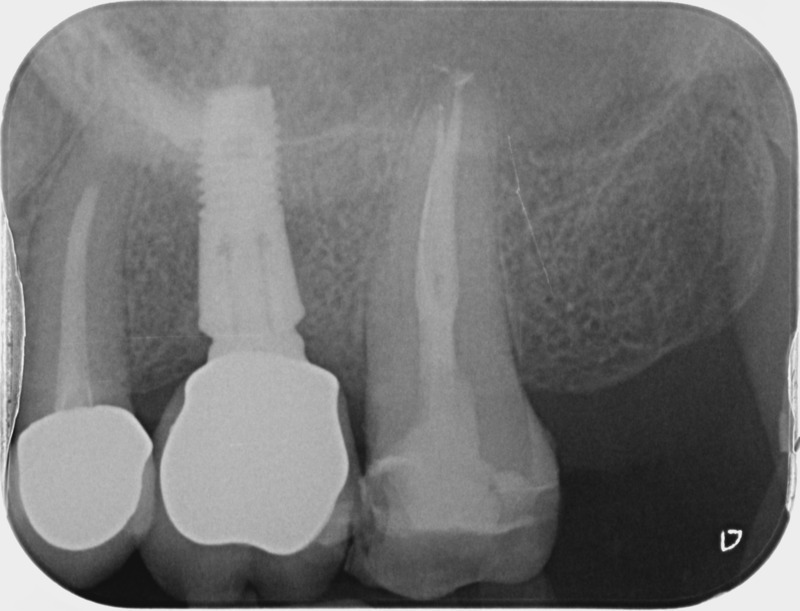

• Reprise de traitement endodontique : La manœuvre consiste à retourner à l’intérieur des racines d’une dent déjà traitée. Il arrive occasionnellement qu’une nouvelle inflammation se déclare suite à une reprise de carie ou une fracture de la dent, ou si le premier traitement endodontique est incomplet. Après s’être assuré que la dent lésée était conservable, il convient de désinfecter de nouveau le réseau canalaire parfois très complexe. La nouvelle obturation des canaux devra être protégée aussi rapidement que possible pour éviter une éventuelle contamination bactérienne.

Avant